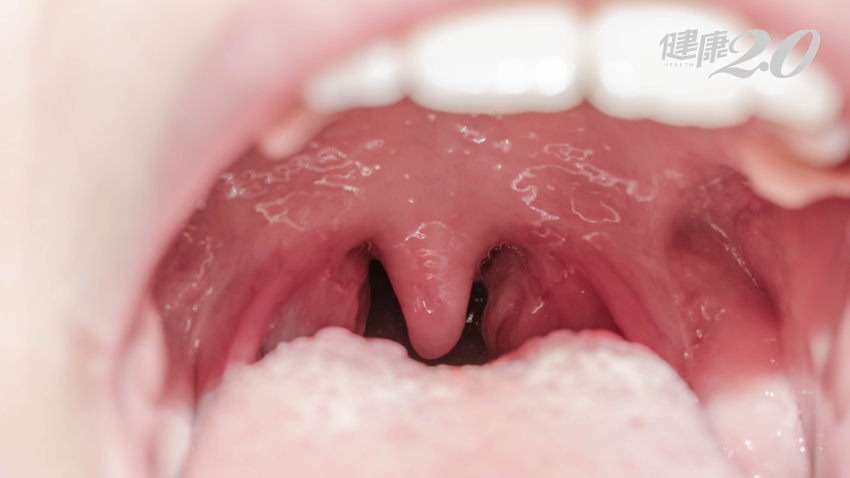

林口長庚醫院耳鼻喉部副教授級主治醫師黃啟哲指出,扁桃腺位在咽喉處,把守人體對外在環境的入口,是對抗外來病菌的第一道防線。扁桃腺周邊滿佈血管、淋巴管、免疫細胞,若發現細菌、病毒入侵時,扁桃腺就會啟動免疫系統消滅它們。

當睡眠不足、免疫力低下時,扁桃腺就可能因細菌或病毒感染,造成扁桃腺發炎,甚至化膿,常見症狀包括扁桃腺紅腫、劇烈喉嚨痛、發燒,少數人會頸部淋巴腫大、耳朵痛等,若患者頻繁且反覆急性扁桃腺發炎,就有可能變成慢性扁桃腺炎,甚至得抽血檢查是否免疫疾病引起。